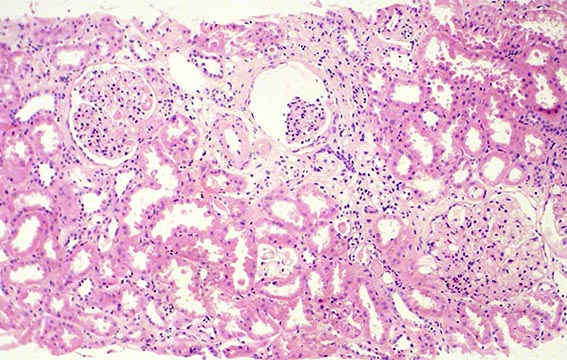

The patient is a 49-year-old man who was kidney transplanted nine years ago. Normal graft function, without proteinuria, until the 8th year, when he started to present mild proteinuria that gradually increased to 2.8 g/24 hours. Serum creatinine has also increased to 1.6 mg/dL.

Other tests: Hb: 9.5 mg/dL, Hto: 30.2 % (he has had multiple transfusions for anemia, since before transplantation), severe dyslipidemia: Triglycerides: 488, total cholesterol 480 mg/dL, VLDL: 209 mg/dL, LDL: 2 mg/dL, HDL: 3 mg/dL. Tests for autoimmunity, complement and viruses: Negative or normal. Ultrasound of the graft: Normal. On examination: Corneas opaque bluish with peripheral white halo, without visual impairment. No other alterations.

See the images of the biopsy.

Figure 1. H&E, X100.